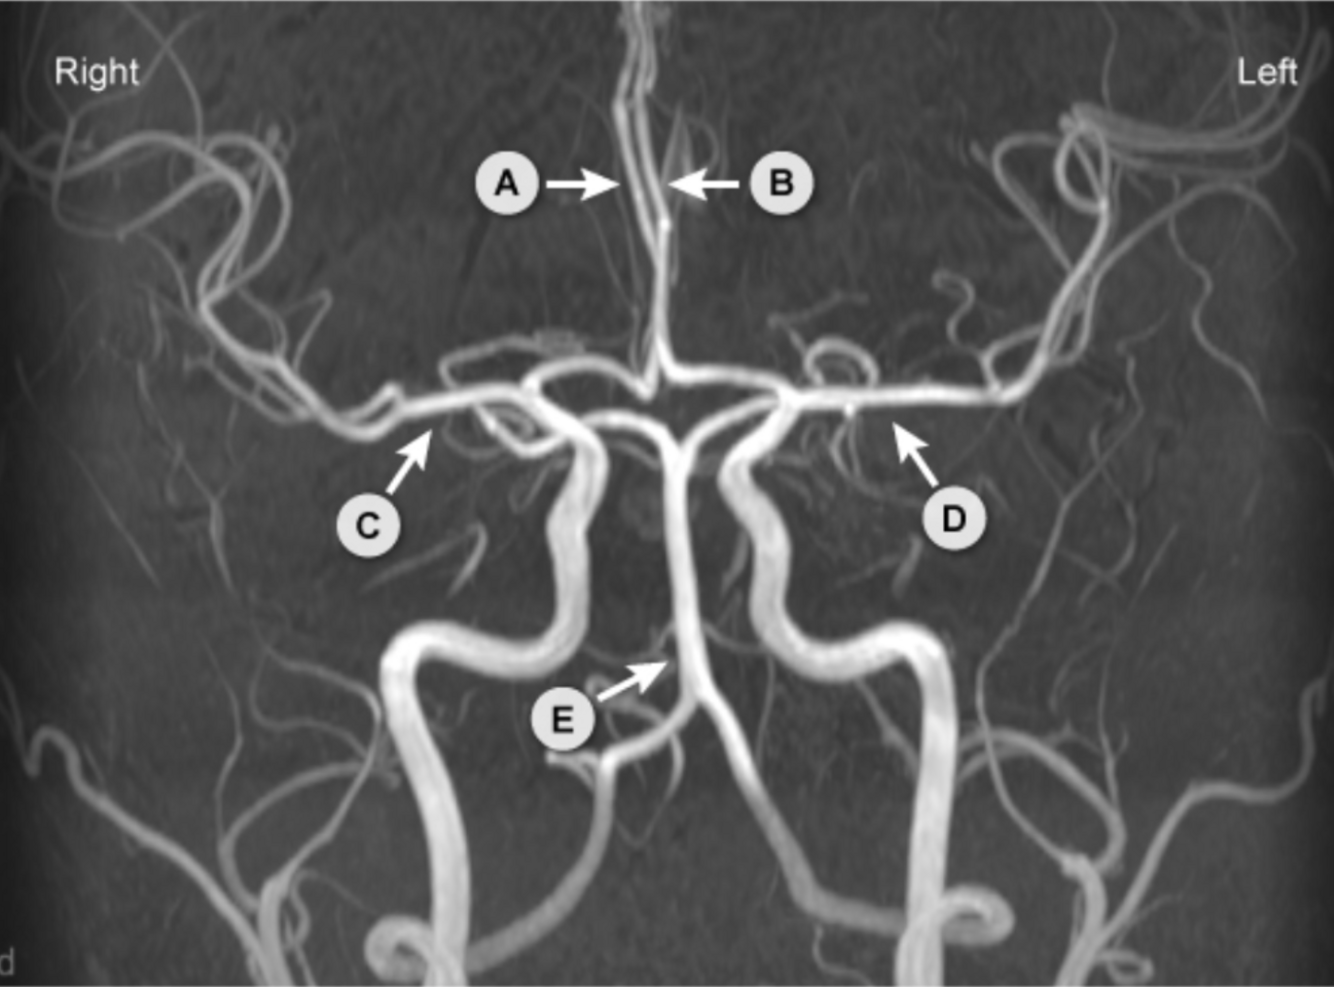

Identifie les structures sur l’image suivante.

A

A : PICA

B : Artères vertébrales

C : AICA

D : Artère basilaire

E : SCA

F : PCA